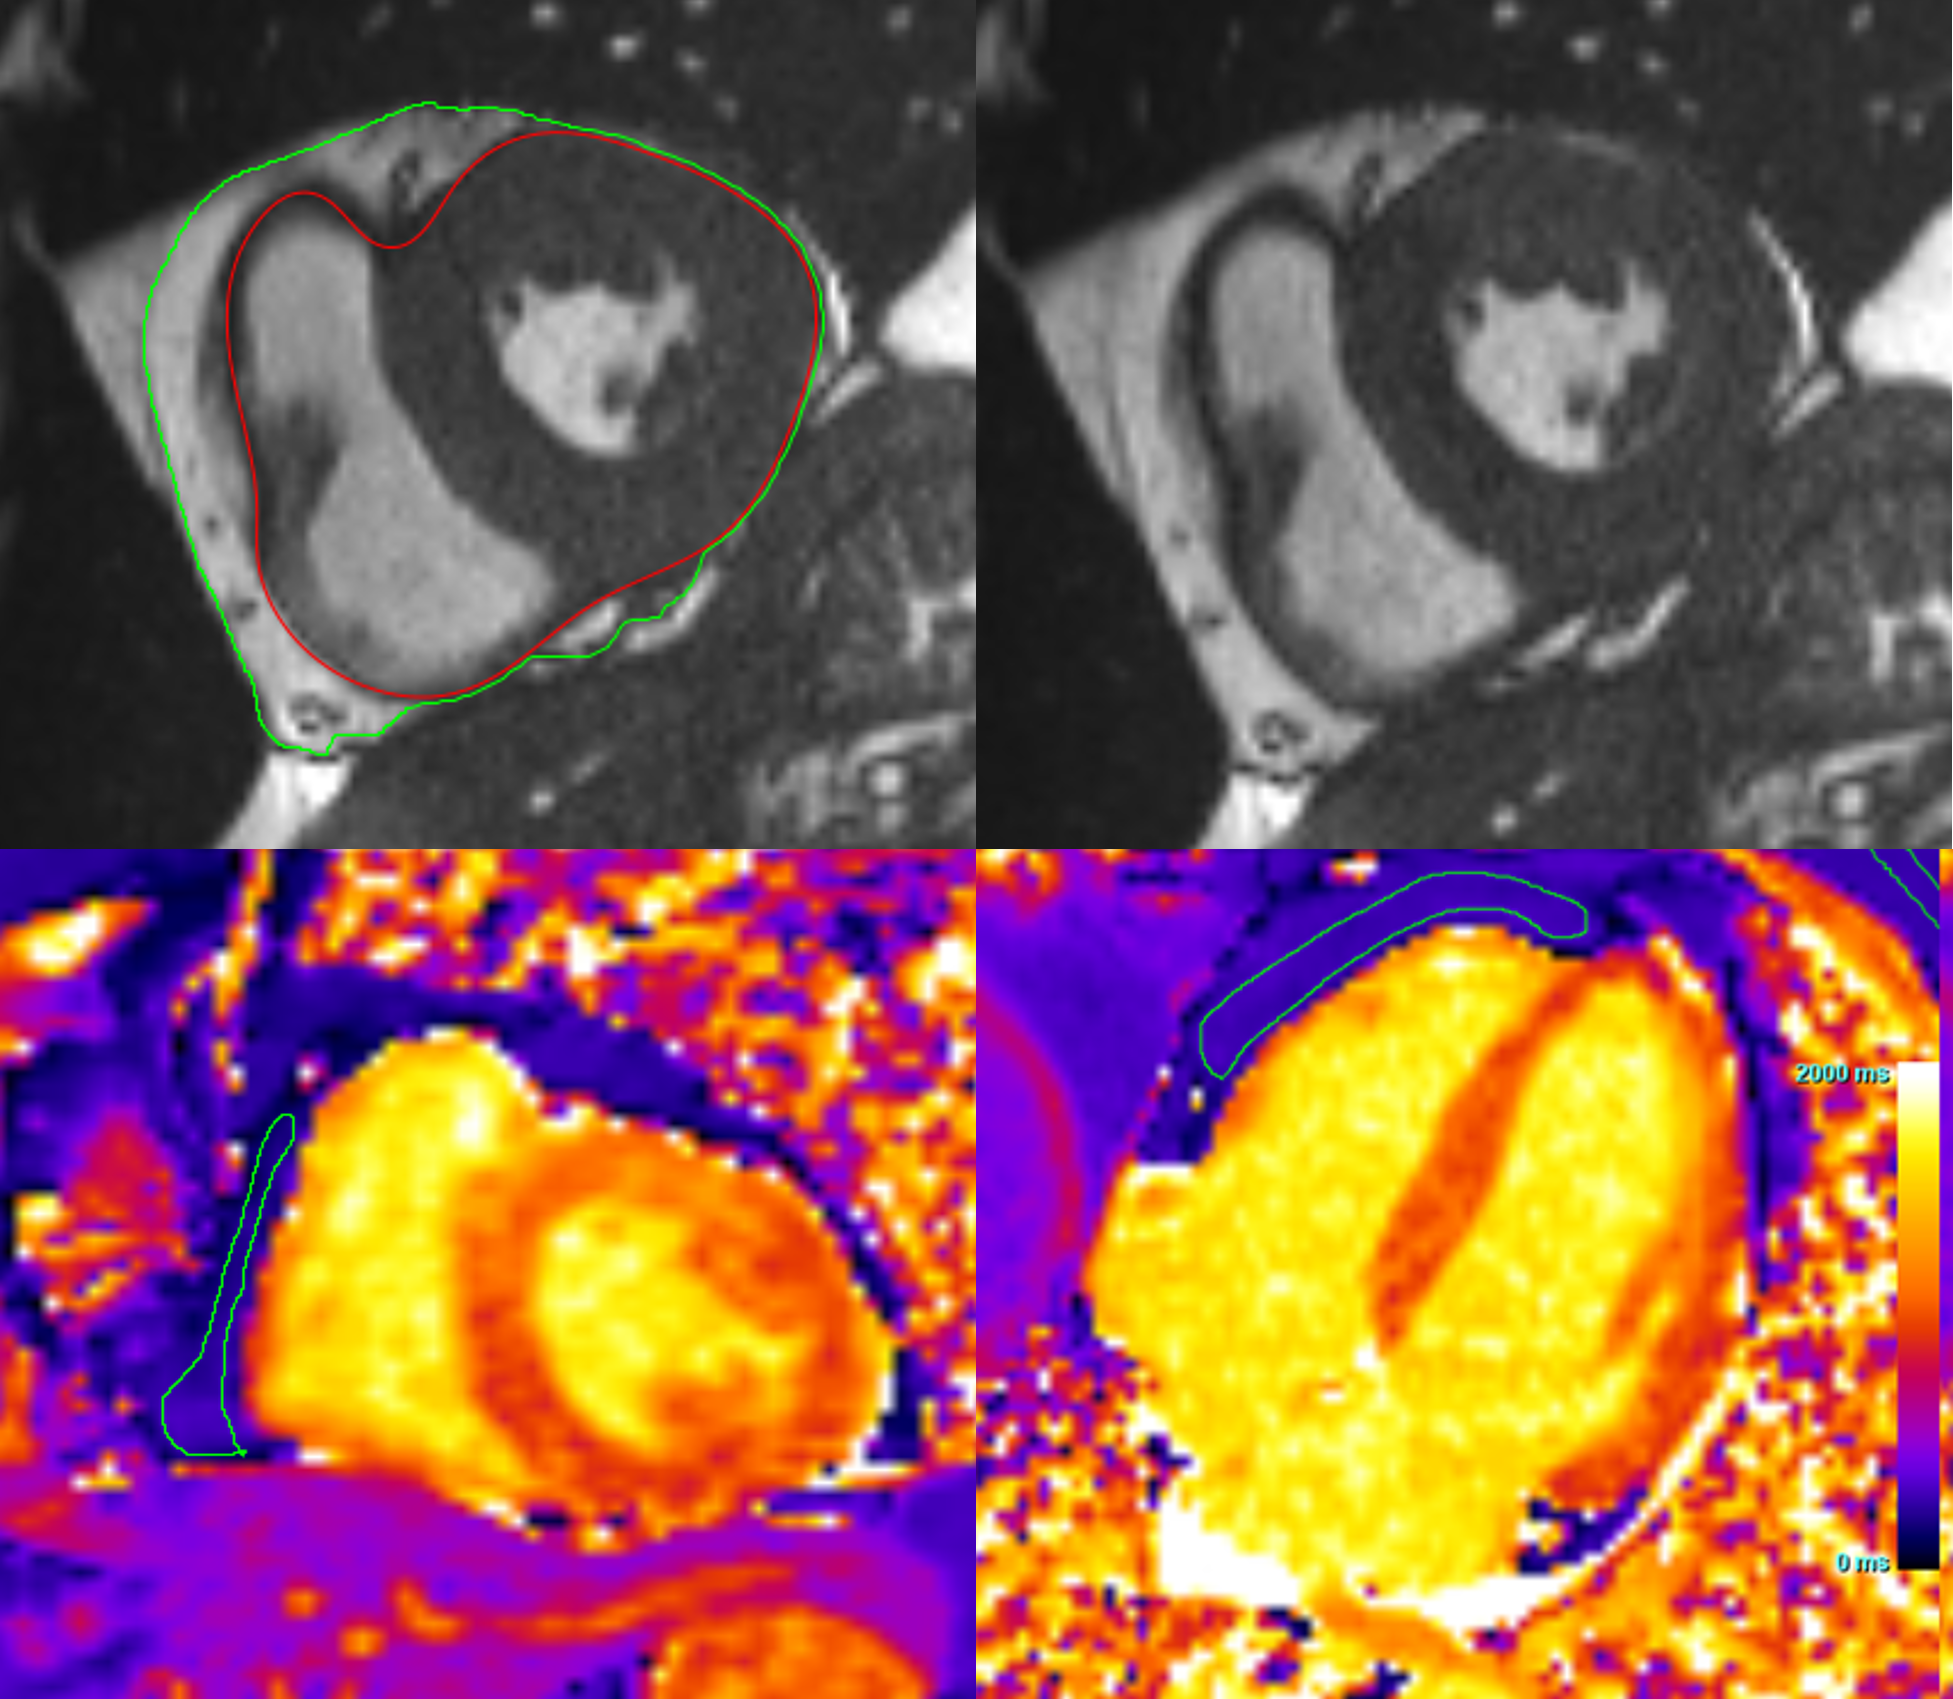

Figure 2: Mean EAT volume analysis across six outcomes including A) VT/VF, B) HF Admission, C) Atrial Fibrillation, D) MACE (composite outcome of VT/VF, HF Admission, and CV Death), E) CV Death, and F) All Cause Death.